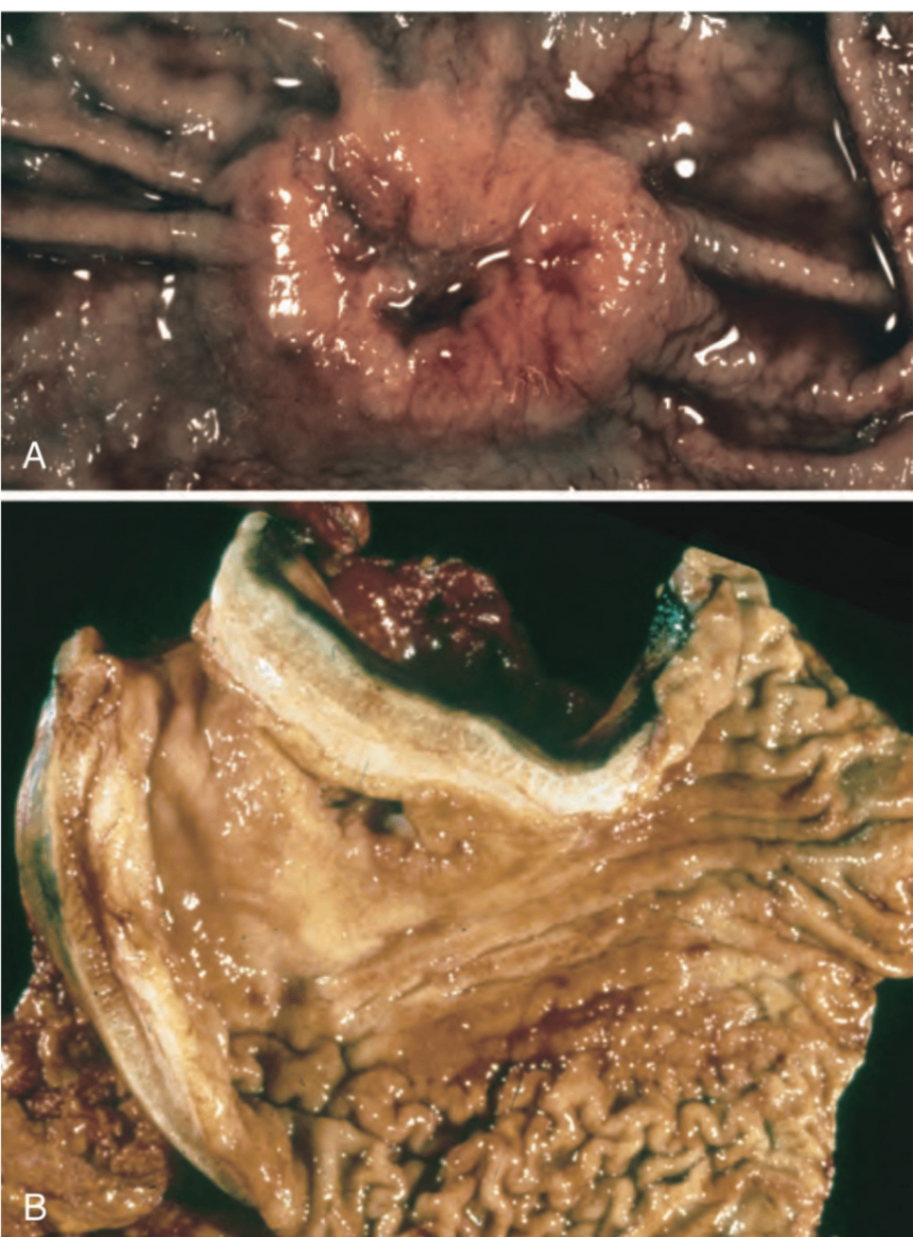

① Intestinal type (장형)

궤양을 동반하는 bulky, exophytic mass를 주로 형성

② Diffuse type (미만형)

• 개별 세포 또는 소집단 형태로 위벽을 광범위하게 침윤; 샘 구조를 형성하지 않음

- 접착력 상실(E-cadherin 소실)로 인해 세포가 유착력을 잃고 discohesive한 형태로 넓게 퍼짐

• 암세포는 큰 점액 공포가 세포질을 밀어내며 signet-ring cell 모양을 이룸

• 침윤 부위에서 섬유반응(desmoplasia)을 유발하여 위벽이 단단해지고 두꺼워짐 → 병변이 광점위할 경우 rugae와 같음 점막의 주름을 소실하고 가죽과 같은 위벽을 형성하며 이를 linitis plastica라고 칭함

A: intestinal-type adenocarcinoma

B: infiltrative type (linitis plastica) gastric cancer

Robbins and Cotran Pathologic Basis of Disease, 10e, pg 775